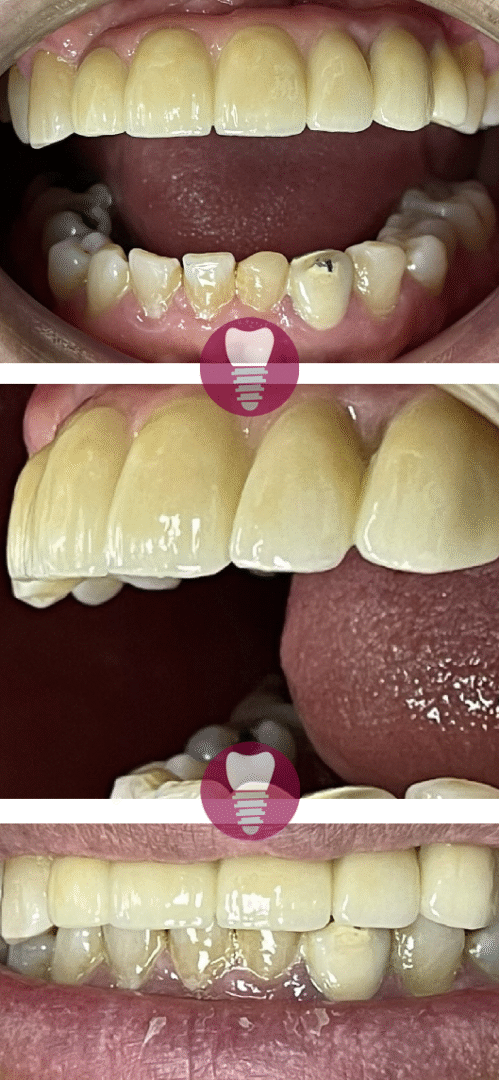

Las carillas dentales son láminas finas de material cerámico o resina compuesta que se adhieren a la superficie de los dientes para mejorar su apariencia. Este tratamiento es ideal para corregir imperfecciones como manchas, fracturas, microdoncia o caries visibles, devolviendo a los dientes un aspecto estético y natural. Las carillas se diseñan a medida, adaptándose al tamaño, color y forma de cada diente para lograr un resultado armonioso y duradero.

1.4 – Carilla de alta estética dental por caries